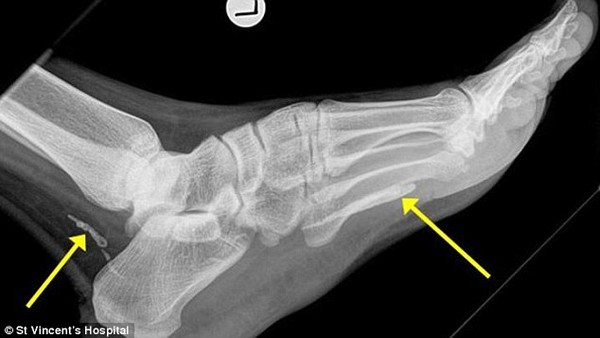

Sau khi tiếp nhận ca nhiễm giun sán của một người đàn ông 38 tuổi gốc châu Phi, các bác sĩ thuộc Bệnh viện St. Vincent tại thành phố Sydney, Úc đã phải công nhận đây là một trong những ca nhiễm trùng kinh hoàng nhất mà họ từng bắt gặp. Hình ảnh chụp X-quang cho thấy con giun chỉ có chiều dài khoảng 1m đã sống hơn 4 năm trong bàn chân của người đàn ông này.

Hình ảnh chụp X-quang bàn chân của người đàn ông Sudan.

Tờ Sydney Morning Herald đưa tin, người đàn ông gốc Sudan đã tới Úc cách đây 4 năm nhưng gần đây, anh mới tới bệnh viện thăm khám vì một bên chân bị phù nề lên sau gần 1 năm đau nhức. Bác sĩ Jonathan Darby, người phụ trách điều trị cho biết, trong bàn chân của người đàn ông này có 2 phần thân của giun chỉ châu Phi, một ở đằng sau mắt cá chân và một ở lòng bàn chân. Theo phán đoán của bác sĩ Darby, có lẽ con giun này đã chết và bắt đầu đang phân hủy.